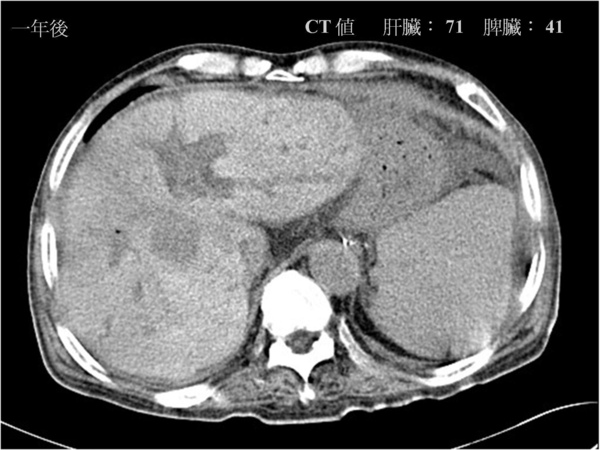

接下來的圖片和方才所見恰好相反。我們可以見到左圖的肝臟顏色變得較明亮(紅色箭頭是肝臟,黃色箭頭是脾臟)。這代表著肝臟的密度增加了。

肝臟負責身體許多的代謝功能,很多種狀況會讓肝臟密度上升。鐵質沉積(hemochromatosis)、銅沉積、或其他藥物及代謝物都可能有如此變化。

這是重度地中海貧血的患者。因為需要長期接受輸血,使得肝臟有過多的鐵質沉積,而逐漸導致肝臟腫大,且密度大大提高。

底下三張圖是逐漸變嚴重的鐵質沉積,肝臟影像逐漸變得明亮,量測到的CT值也逐漸上升。